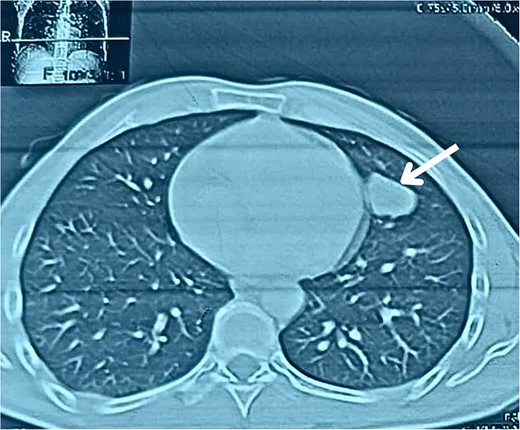

A 38-year-old male educator and part-time farmer with no notable cancer history in his family and a non-smoking background sought medical attention. His medical records included a left inguinal hernia repair two years prior and an ischemic stroke six years ago, for which he was undergoing ongoing treatment with clopidogrel, aspirin, and rosuvastatin. The patient reported swelling in the right inguinal region, without any other symptoms. The patient was prepared for surgery to repair the hernia. Upon opening the hernial sac, a thickened wall was observed. Aspiration was conducted to exclude bladder involvement, yielding cloudy, serous fluid indicative of ascites and omental thickening. Based on these observations, samples from the hernial sac wall (peritoneum), omentum, and ascitic fluid were submitted for histopathological analysis, and the hernia was repaired (Fig. 1). Peritoneal surgical biopsy showed that the peritoneal tissue fragments involved epithelioid cell malignant neoplasms with tubular and papillary formations and stromal infiltration. An IHC study revealed Calretinin and CK5/6 markers (mesothelial cell markers) were diffusely positive in the tumor, leading to a diagnosis of malignant mesothelioma. (Fig. 2 and 3) CEA levels were assessed and found to be within the normal limits. Contrast-enhanced computed tomography (CT) of the chest, abdomen, and pelvis revealed a 58 × 31 mm lobulated mass with multiple septate cavities in the lateral and basal pleura of the left lower lobe (Figs 4–6). The scan also showed thickening of the omentum, mesentery, and peritoneum, consistent with a left pleural mesothelioma with peritoneal and omental metastases. Oncologists diagnosed the patient with stage 4 pleural mesothelioma. The patient was determined to require oncological treatment consisting of eight cycles of cisplatin combined with gemcitabine. Unfortunately, the patient died during the fourth chemotherapy cycle.